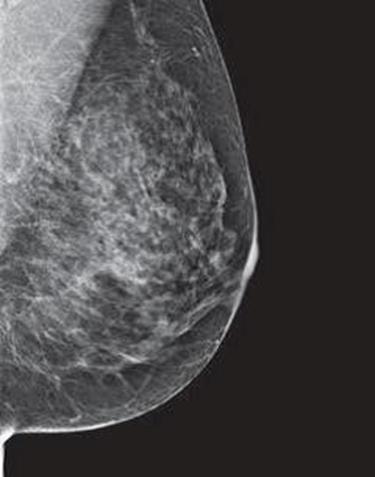

Dense breast tissue, as seen on a mammogram, has more fibrous connective tissue and glandular tissue, and less fatty tissue. It is often inherited, but menopausal hormone therapy, and low body mass index are factors associated with breast density. Dense breast tissue is a risk factor for breast cancer, and a radiologist can tell if a woman has dense breasts.

A mammogram uses X-rays (ionizing radiation) to create images of the inside of the breast to check for cancer and other conditions. It can be used for screening to detect cancer, for instance, before there’s a lump in the breast, or to assist in the diagnosis of cancer. Radiologists use mammograms to interpret, and classify breast density into four categories.

A, B, C, D’s of Breast Density and Mammograms

Dense breasts are common findings after a mammogram, and are not considered a disease, or an abnormal condition. However, they are a risk factor for a woman to develop breast cancer. According to doctors at Memorial Sloan Kettering, women with extremely dense breast tissue “are four to six times more likely to get breast cancer than people with the least dense breasts.”